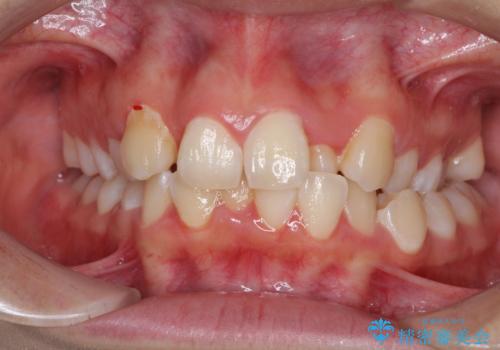

- 骨格的な咬み合わせのズレ、前歯のデコボコとクロスバイトを気にして来院された患者様です。

口元の突出感が若干あり口が閉じにくく、デコボコが強いため、上下左右の小臼歯計4歯を抜歯し、ワイヤー装置による矯正治療を行うこととしました。